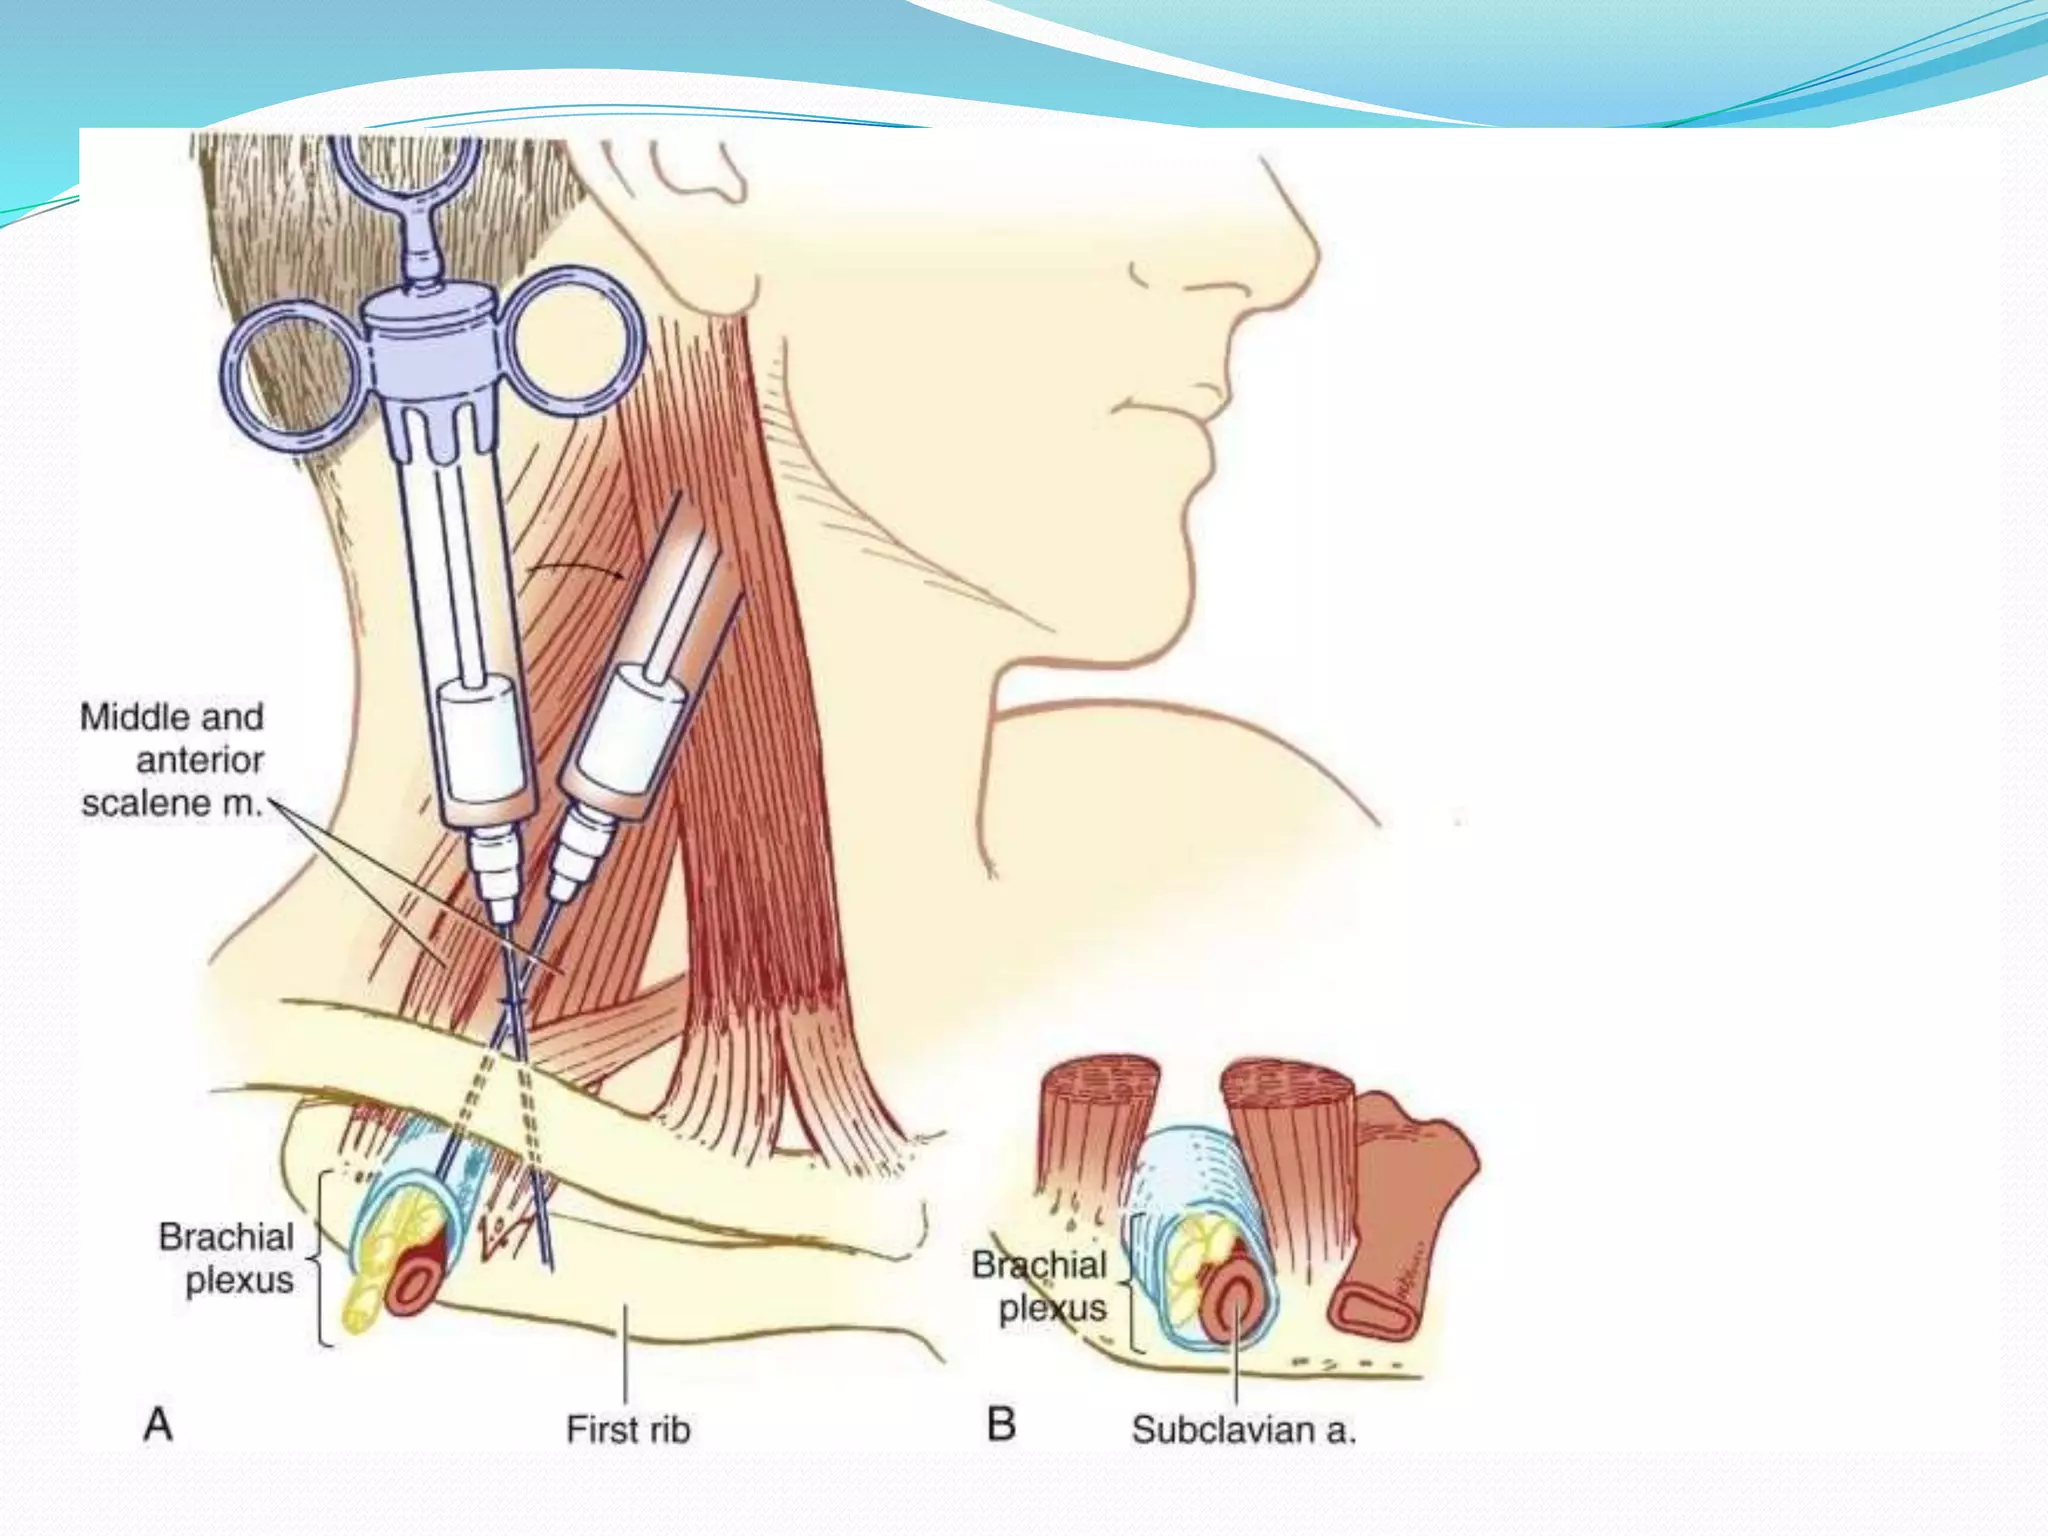

This document provides an overview of brachial plexus anatomy and techniques for brachial plexus nerve blocks. It begins with a description of the brachial plexus formation from cervical and thoracic nerve roots and its branching pattern. Four main approaches for brachial plexus nerve blocks are described: interscalene, supraclavicular, infraclavicular, and axillary. Details are provided on the anatomy and techniques for performing interscalene and supraclavicular brachial plexus blocks. Ultrasound guidance is discussed as an advancement which allows real-time visualization of needle and nerve. Complications are also summarized.